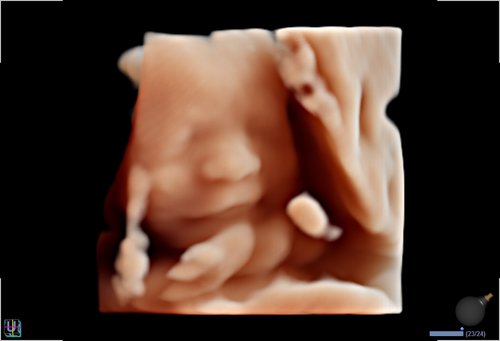

• Volume Master, Volume Advance, Live HQ, Auto NT (Geburtshilfe)

• 3D/4D-Modus